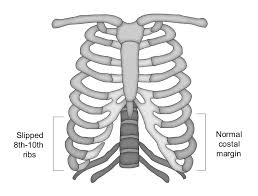

갈비뼈 금간 상태는 외부 충격이나 반복적인 압박으로 인해 뼈에 미세한 균열이 생긴 것을 말합니다. 단순 타박상과 달리 통증이 심하고 숨을 쉴 때, 기침을 할 때 더 크게 아파 일상생활에 불편을 줍니다. 방치할 경우 골절로 진행되거나 폐 손상 같은 합병증으로 이어질 수 있어 주의가 필요합니다.

1. 갈비뼈 금간 증상 ⚡

갈비뼈 금간 증상